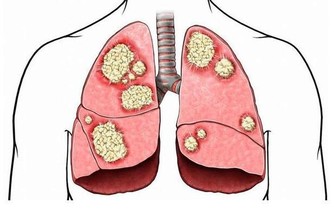

蘑菇作為菌類,它的營養價值和功效往往要高於其他蔬菜,蘑菇含多醣類、維生素類等。

有實驗證明,其多醣有調節免疫、抗腫瘤的作用,肝病病人宜常食用之。